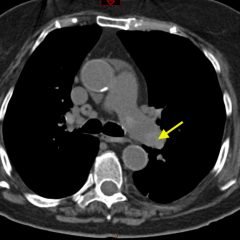

Radiographs demonstrated posterior displacement of the humeral head on the “Y” view (see white arrow) and widening of the glenohumeral joint space on anterior-posterior view (see red arrow). The findings were consistent with posterior dislocation and a Hill-Sachs type deformity.  Sedation was performed and reduction was attempted using external rotation, traction counter-traction. An immediate “pop” was felt during the procedure. Post-procedure radiographs revealed a persistent posterior subluxation with interlocking at posterior glenoid. CT revealed posterior dislocation with acute depressed impaction deformity medial to the biceps groove with the humeral head perched on the posterior glenoid, interlocked at reverse Hill-Sachs deformity (see blue arrow).